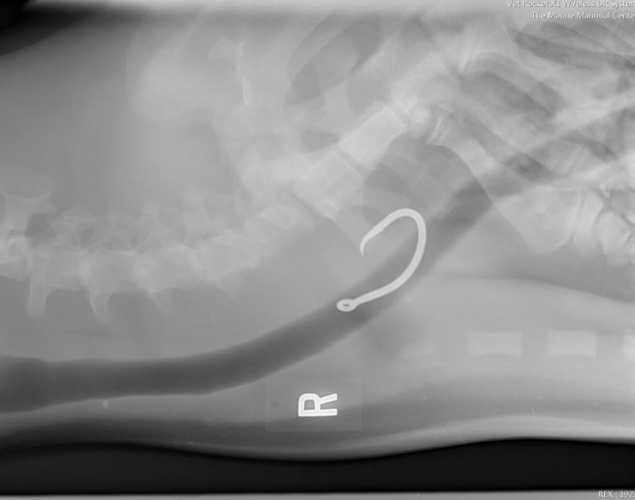

An X-ray of the animal’s throat and chest, taken with a portable Vet Rocket X-ray machine, had confirmed that the seal had ingested a large fishing hook, which had become embedded in the lining of his esophagus.

The veterinary team examining RF28, led by Dr. Gregg Levine and other experts from the NOAA Fisheries Hawaiian Monk Seal Research Program, knew that the ingested hook would be deadly if not removed. After stabilizing the sleeping seal, they moved quickly but carefully as they began the de-hooking procedure.

Hawaiian monk seals have a fairly tough esophagus because they are accustomed to swallowing fish whole, so the team was hopeful that they could remove the hook by pulling it out through the seal’s mouth rather than having to open his body cavity, a much riskier procedure.

Using an endoscope that allowed the team to see what they were doing inside the seal’s throat, they were able to snake a de-hooking tool down the esophagus to locate and dislodge the hook.

After several hours of delicate maneuvering, the two-inch hook was successfully removed. But the surgery—and the danger to the monk seal—wasn’t over yet.